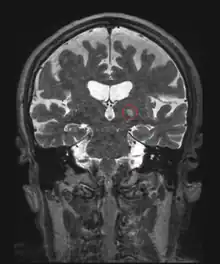

Neurological disorders

One of the first applications of HIFU was the treatment of Parkinson's disease in the 1940s. Although ineffective at the time, HIFU has the capacity to lesion pathology. A focused ultrasound system is approved in Israel, Canada, Italy, Korea and Russia to treat essential tremor,[6] neuropathic pain,[7] and Parkinsonian tremor.[8] This approach enables treatment of the brain without an incision or radiation. In 2016, the US Food and Drug Administration (FDA) approved Insightec's Exablate system to treat essential tremor.[9] Treatment for other thalamocortical dysrhythmias and psychiatric conditions are under investigation.[10]